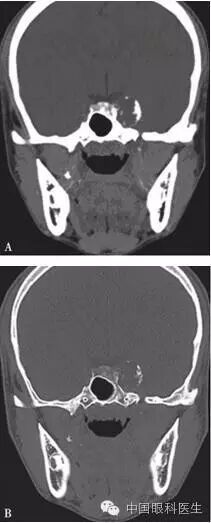

体格检查:双眼矫正视力0.8。右眼眼睑位置及眼球运动均正常,左眼上睑下垂,遮盖瞳孔上半部分,提上睑肌肌力4mm,左眼不能外展,上转、下转、内收运动均部分受限。患者右眼瞳孔直径3mm,左眼4mm;右眼对光反射灵敏,左眼迟钝,RAPD(-)。双眼眼底、眼压均正常。视觉诱发电位(visual evoked potential,VEP)、视野检查均未见明显异常。头颅MRI平扫+增强结果显示,左侧鞍旁海绵窦内T1WI稍低信号、T2WI稍高信号影,大小为21mm×23mm×22mm,增强扫描病灶呈不均匀强化,内可见多发的未强化区,左侧颈动脉海绵窦段受压外移,但结构未见明显损害(图2-3-0-1)。头颅CT平扫显示左侧鞍旁密度减低影,CT值为21Hu,大小为2.3cm,边缘可见钙化影,双侧眶内和球后未见异常(图2-3-0-2)。患者转入神经外科并行经额颞颧弓硬膜外入路左侧海绵窦区占位性病变切除术。术中快速冰冻切片病理学检查示,切除的组织标本富含黏液,制片困难。术后病理报告:左侧海绵窦区软骨源性肿瘤。考虑软骨瘤可能性大,局部细胞生长活跃,细胞间质伴黏液变性,免疫组织化学染色显示,肿瘤细胞对S-100和CK均呈阴性反应(图2-3-0-3)。术后患者左眼视力下降,额部及颊部皮肤感觉迟钝。眼科检查:右眼检查同术前,左眼矫正视力0.5,角膜上皮粗糙,角膜荧光素染色弥漫性着色,RAPD(-)。检眼镜检查示视盘界清,色红,视网膜血管走行正常,黄斑区未见明显异常。VEP、视野检查均未见明显异常。给予玻璃酸钠滴眼液点左眼、重组牛碱性成纤维细胞生长因子软膏涂左眼结膜囊并给予营养神经、改善全身血液循环药物治疗1周后,检查示见角膜上皮透明,角膜荧光素染色不明显,矫正视力0.8,左眼提上睑肌肌力测试可上提10mm。术后1个月复诊见,上睑下垂治愈,眼球运动受限明显好转。

注:A.软组织窗;B.骨窗。左侧鞍旁可见密度减低影,CT值21Hu,大小约为2.3cm,边缘可见钙化影,双侧眶内和球后未见异常